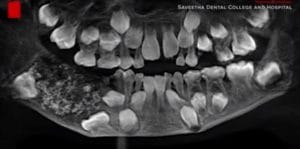

526 denti trovati nella bocca di un bambino di 7 anni in India.

I dentisti dell’ospedale hanno estratto oltre 500 denti dalla sua bocca, in un’operazione durata circa 5 ore, durante la quale i medici hanno trovato dei denti “anormali”, diversi dai molari che normalmente crescono nella bocca dei bambini adulti.

I medici del Saveetha Dental College and Hospital di Chennai hanno dichiarato che si tratta del primo caso di questo tipo mai documentato al mondo. Le dimensioni dei denti andavano da 0,1 a 15 millimetri.

Stando alla Tac prescritta dai dottori prima dell’intervento, a generare la crescita esponenziale di denti all’interno della bocca del bambino di 7 anni, è stata una specie di sacca: una sorta di tumore che impediva la crescita regolare dei molari del piccolo, al cui interno erano invece racchiusi i 526 denti anormali.